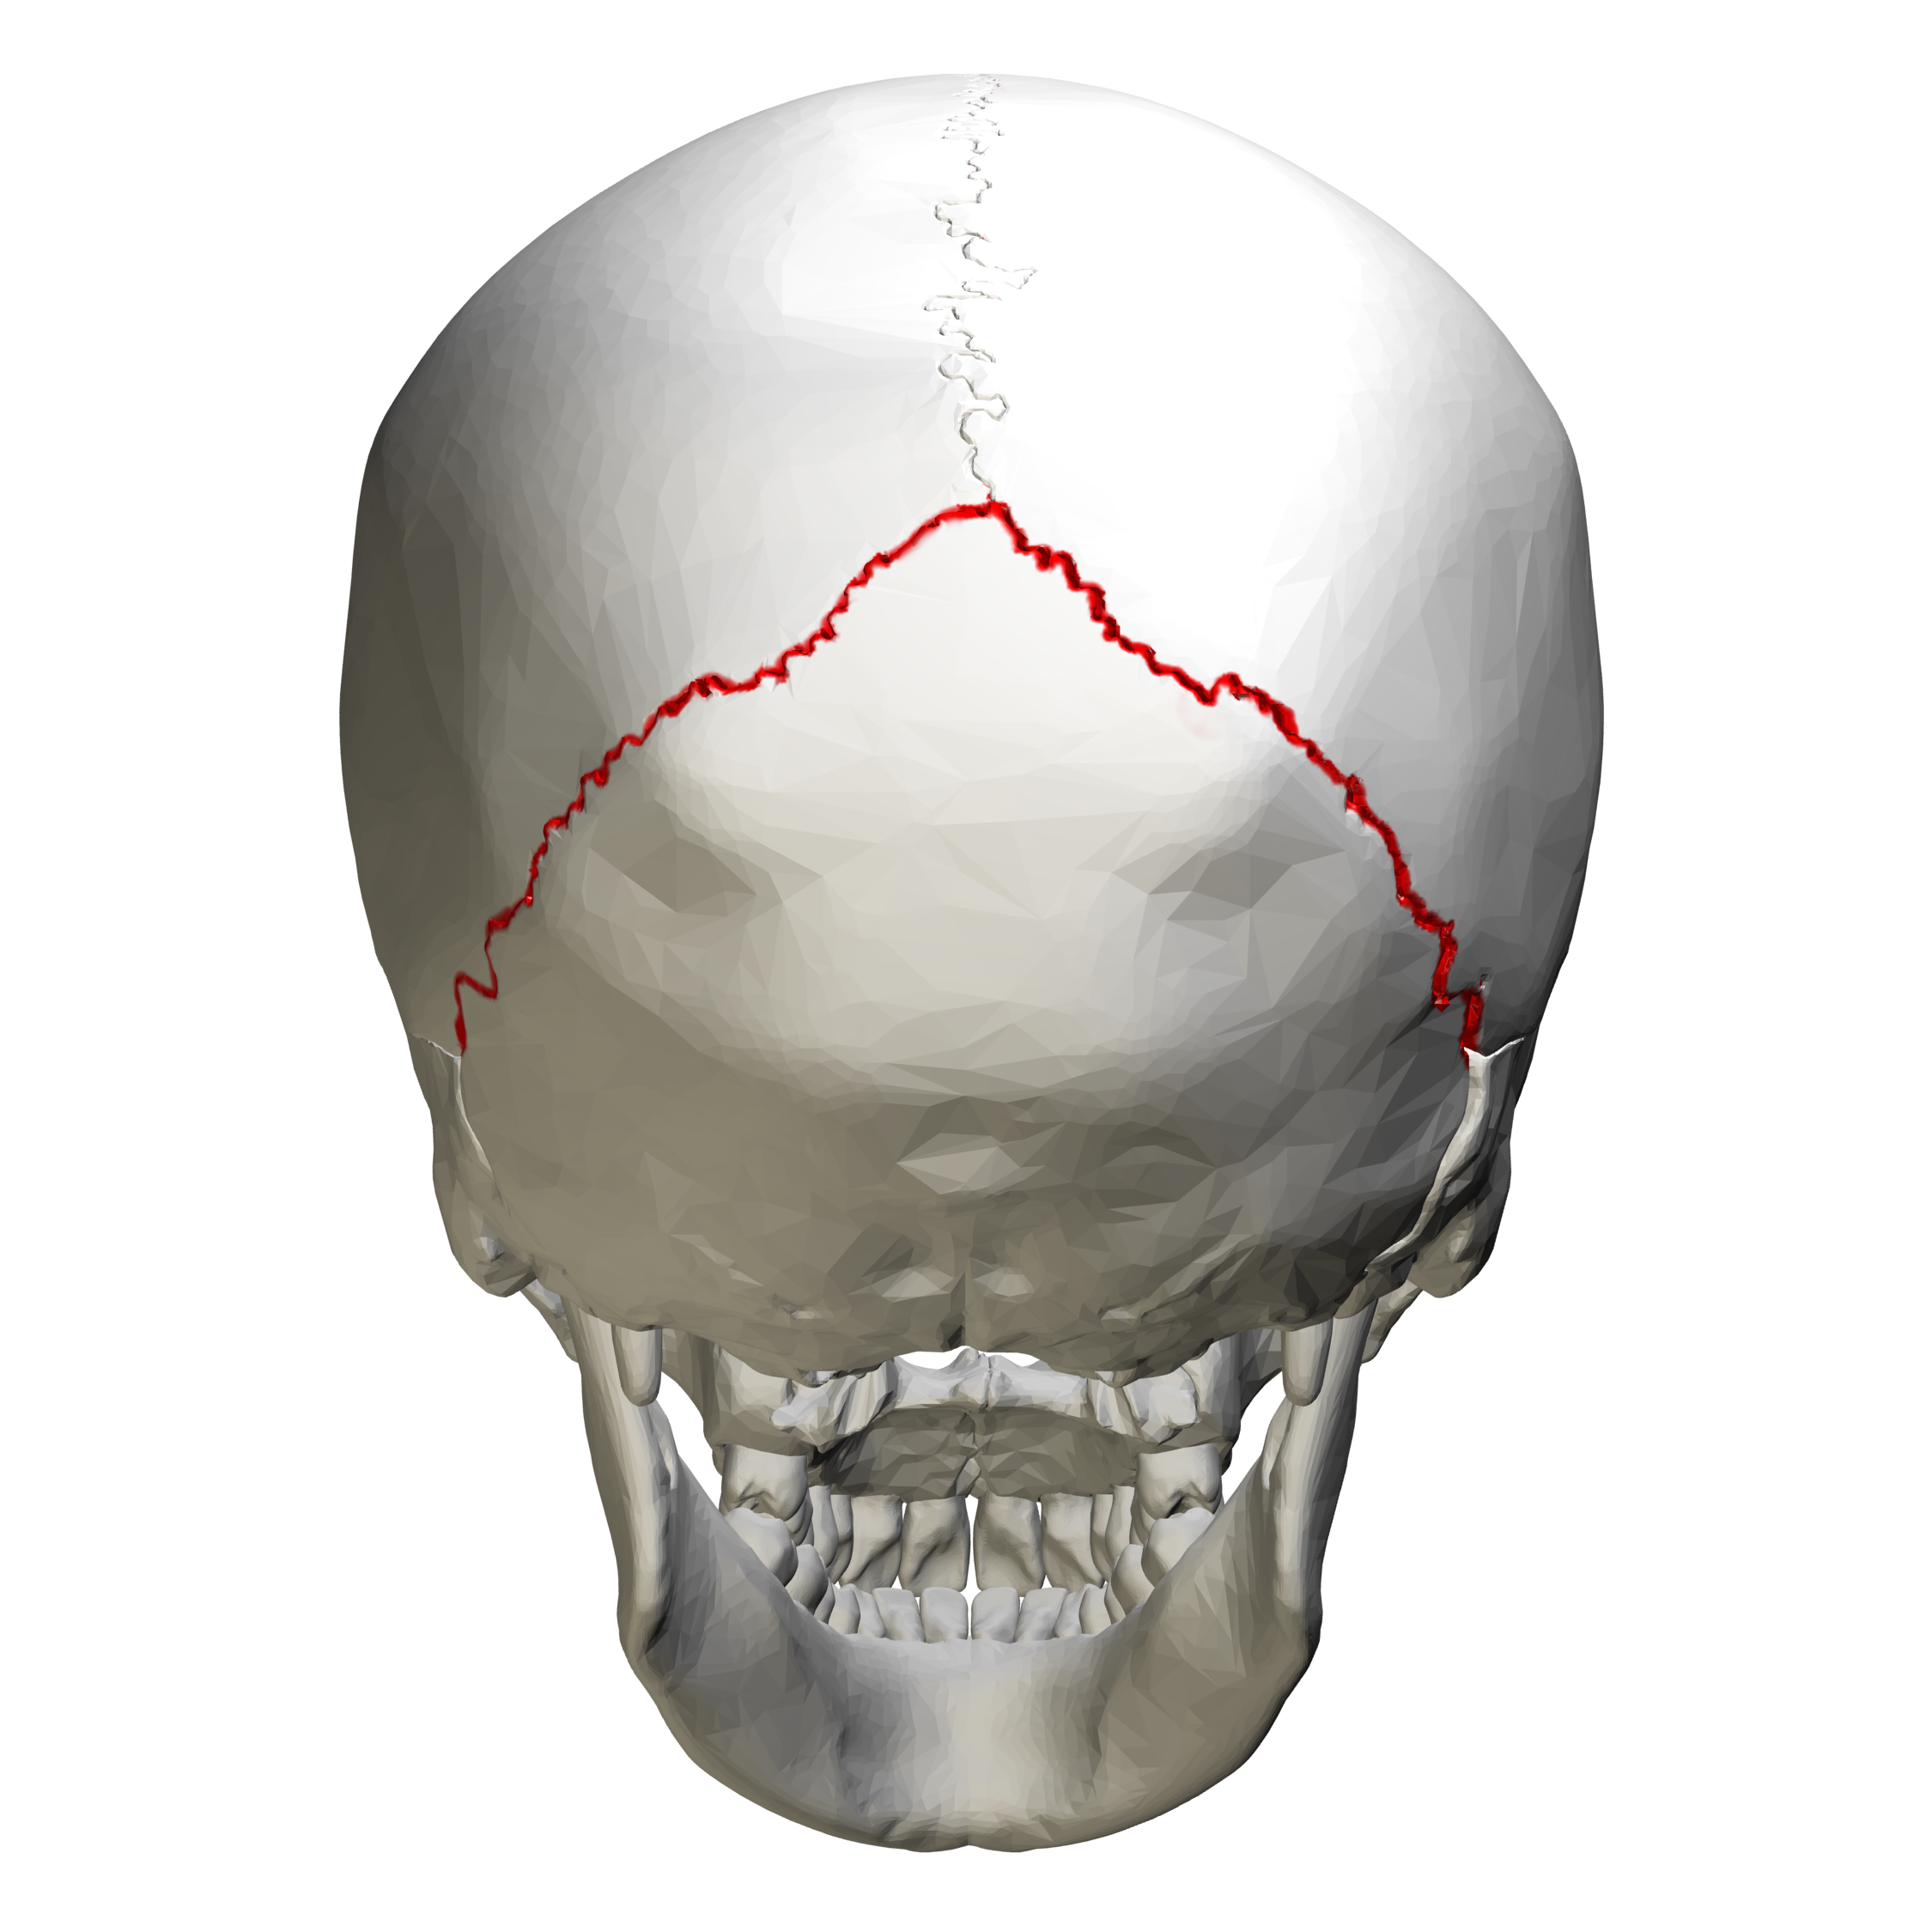

What are skull sutures?

Interlocking immovable joints of the skull

What suture is this?

Lambdoidal Suture

What do sutures tell you about the skull?

It shows that the skull is made up of more than one bone